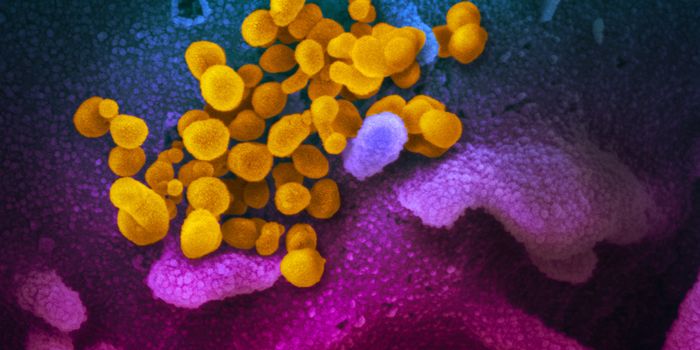

SEP 25, 2021Health & MedicineAfter a year-long study, researchers have assembled a detailed narrative about how the SARS-Cov-2 virus has spread on th ...

DEC 24, 2020MicrobiologyThe UK recently reported that it had detected a new variant of the SARS-CoV-2 pandemic virus, which causes COVID-19. Thi ...